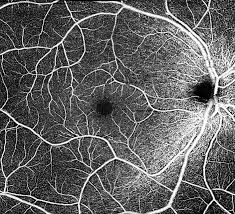

Con el advenimiento de la tomografía de coherencia óptica de dominio espectral (SD-OCT), es posible obtener imágenes del segmento posterior del ojo rápidamente en múltiples ubicaciones anatómicas incluida la cabeza del nervio óptico (ONH), la capa de fibras nerviosas de la retina circumpapilar (cp-RNFL) y la mácula. Ver más…

La tomografía de coherencia óptica se ha convertido en el sistema de imagen más común para detectar de manera precoz el daño glaucomatoso; de ahí que resulte imprescindible para las decisiones clínicas y como criterio de inclusión en investigaciones y ensayos clínicos.